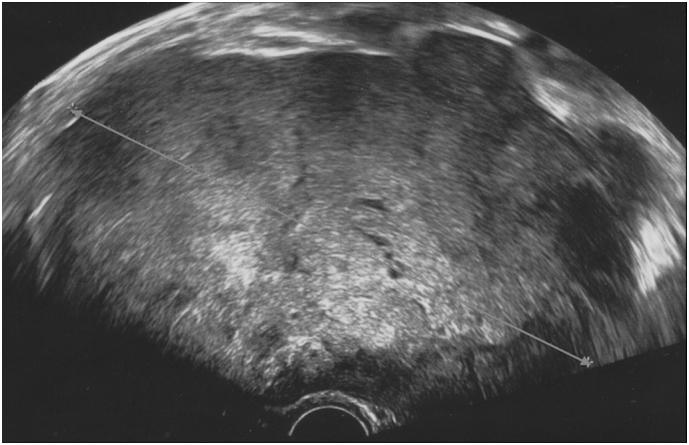

We describe a case of an 80-year-old woman with ovarian metastasis of MCC six years after excision of a cutaneous MCC on the cheek.

我们描述了一例80岁女性病例,其在面颊部皮肤MCC切除术后六年出现卵巢转移。